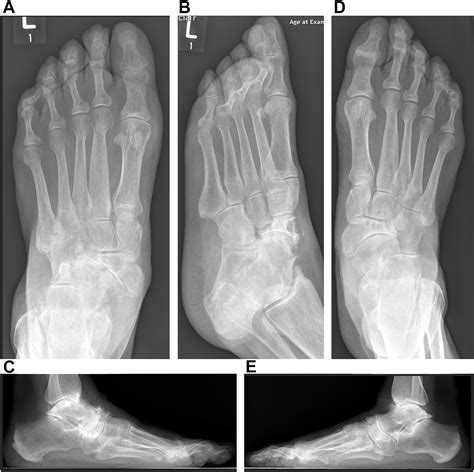

Mueller Weiss Syndrome is a rare degenerative disease of the navicular bone, a small, boat-shaped bone located in the midfoot. Unlike fractures caused by acute trauma, this syndrome occurs when the bone loses its blood supply, leading to fragmentation and collapse. While the exact cause remains somewhat elusive, it is frequently associated with mechanical stress, congenital anomalies, or systemic conditions that impede vascular flow.

Typically, the syndrome affects adults between the ages of 40 and 60. Patients often present with persistent pain on the inner (medial) side of the foot, which gradually worsens with weight-bearing activities. As the navicular bone begins to collapse, the structural integrity of the foot’s arch is compromised, often leading to a secondary flatfoot deformity.

Diagnosing Mueller Weiss Syndrome requires a comprehensive evaluation by a foot and ankle specialist. Because the symptoms can mimic other conditions like tarsal coalition or arthritis, imaging is essential for a precise diagnosis.

X-ray (Weight-bearing) The primary tool to visualize the navicular bone's fragmentation and collapse.